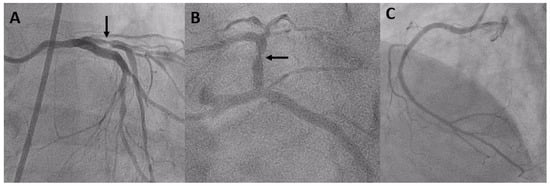

- Castagna, M.T.; Mintz, G.S.; Weissman, N.; Maehara, A.; Finet, G.; Waksman, R. "Black hole": Echolucent restenotic tissue after brachytherapy. Circulation 2001, 103, 778. [Google Scholar] [CrossRef] [PubMed]

- Otsuka, Y.; Murata, T.; Kono, M.; Imoto, H.; Koyama, T.; Nakamura, K.; Kadama, S.; Noguchi, H.; Saito, T. Black hole restenosis after drug-eluting stent implantation for in-stent restenosis: Potential mechanism and optimal strategy. Heart Vessels 2015, 30, 682–686. [Google Scholar] [CrossRef] [PubMed]

- Kurita, T.; Terashima, M.; Suzuki, T. Serial optical coherence tomography imaging of the “black-hole” phenomenon by intravascular ultrasound following sirolimus-eluting stent implantation. EuroIntervention 2012, 7, 1480–1481. [Google Scholar] [CrossRef] [PubMed]